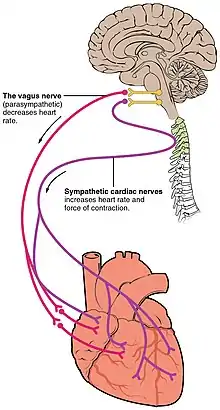

Nerve supply

The heart receives nerve signals from the vagus nerve and from nerves arising from the sympathetic trunk. These nerves act to influence, but not control, the heart rate. Sympathetic nerves also influence the force of heart contraction.[35] Signals that travel along these nerves arise from two paired cardiovascular centres in the medulla oblongata. The vagus nerve of the parasympathetic nervous system acts to decrease the heart rate, and nerves from the sympathetic trunk act to increase the heart rate.[7] These nerves form a network of nerves that lies over the heart called the cardiac plexus.[7][34]

The vagus nerve is a long, wandering nerve that emerges from the brainstem and provides parasympathetic stimulation to a large number of organs in the thorax and abdomen, including the heart.[36] The nerves from the sympathetic trunk emerge through the T1-T4 thoracic ganglia and travel to both the sinoatrial and atrioventricular nodes, as well as to the atria and ventricles. The ventricles are more richly innervated by sympathetic fibers than parasympathetic fibers. Sympathetic stimulation causes the release of the neurotransmitter norepinephrine (also known as noradrenaline) at the neuromuscular junction of the cardiac nerves. This shortens the repolarisation period, thus speeding the rate of depolarisation and contraction, which results in an increased heart rate. It opens chemical or ligand-gated sodium and calcium ion channels, allowing an influx of positively charged ions.[7] Norepinephrine binds to the beta–1 receptor.[7]